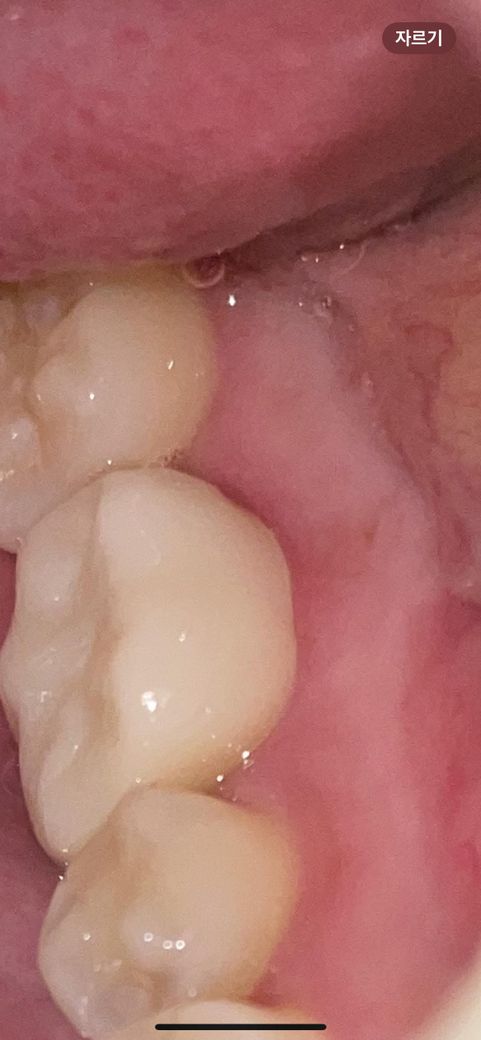

• 2번 째 사진

목동안치과의원

크라운 보철물을 부착하고 나서는 크라운의 경계부분이 떠 있는 듯한 느낌이 들 수 있습니다. 대부분 크게 문제가 되지 않기 때문에 양치질을 꼼꼼히 해주 그래서 이루어진다면 큰 문제가 생기지 않을 것으로 생각됩니다

• 크라운 치료시에 어느정도 틈이 생기는 것은 문제가 되지 않습니다. 해당부위 음식물찌꺼기가 남지 않도록 꼼꼼히 양치를 하고, 정기적으로 치과에 방문하여 스케일링 치료를 받길 권합니다.

• 저정도 크라운과 잇몸 사이 틈의 경우에는 잇몸이 어느정도 회복되면서 덮이게 됩니다 크라운 치료를 하다보면 어느정도 잇몸에 상처가 날 수 있는데 지금 그런 정도인 것 같습니다

치실로 크라운과 옆 치아 사이 치실질을 해주면 잔여 접착제가 나올 순 있습니다